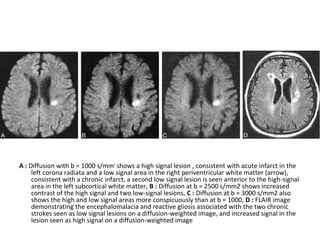

A : Diffusion with b = 1000 s/mm2

shows a high signal lesion , consistent with acute infarct in the

left corona radiata and a low signal area in the right periventricular white matter (arrow),

consistent with a chronic infarct, a second low signal lesion is seen anterior to the high-signal

area in the left subcortical white matter, B : Diffusion at b = 2500 s/mm2 shows increased

contrast of the high signal and two low-signal lesions, C : Diffusion at b = 3000 s/mm2 also

shows the high and low signal areas more conspicuously than at b = 1000, D : FLAIR image

demonstrating the encephalomalacia and reactive gliosis associated with the two chronic

strokes seen as low signal lesions on a diffusion-weighted image, and increased signal in the

lesion seen as high signal on a diffusion-weighted image